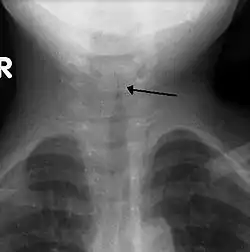

En frontal røntgenundersøgelse af halsen udføres ikke rutinemæssigt,[4] men hvis den foretages, kan den vise en karakteristisk indsnævring af luftrøret, som kaldes kirketårnstegnet på grund af den subglottiske stenose, som i form ligner et kirketårn. Kirketårnstegnet antyder diagnosen, men er fraværende i halvdelen af tilfældene.[3]